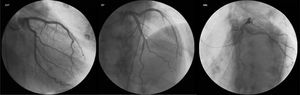

Durante o internamento na Enfermaria de Cardiologia, um cateterismo cardíaco diagnóstico foi realizado, com coronárias sem lesões (Figura 2). Não havia história familiar de IC, miocardiopatia ou morte súbita. O doente negava história recente de infeção viral ou bacteriana e nunca havia viajado para fora do país. O estudo laboratorial foi negativo, nomeadamente para vírus da imunodeficiência humana e hepatotrópicos. A função tiroideia não demonstrava alterações (avaliações prévias ao longo do seguimento na consulta de diabetes também normais), não tendo sido avaliados anticorpos antitiroideus neste contexto. Ressalvam‐se ainda outros parâmetros laboratoriais ao longo do internamento: hemoglobina (Hb) à admissão de 15g/dl, com nadir de 13g/dl, sem perdas hemáticas objetivadas; sem ferropénia funcional ou absoluta (Ferritina 326ng/mL) e sem défice de ácido fólico ou vitamina B12 (5,9ng/mL e 590pg/mL, respetivamente); vitamina B1 avaliada por protocolo nos doentes com IC / disfunção ventricular esquerda de 28ng/mL (N 16‐48). Sete dias após admissão hospitalar, um novo ETT foi realizado: ventrículo esquerdo não dilatado, com compromisso ligeiro da função sistólica (FEj estimada em 46%), com strain global longitudinal ligeiramente reduzido (‐16%) (Figura 3). Foi proposta a realização de ressonância magnética cardíaca, que o doente recusou. À data de alta hospitalar, o doente encontrava‐se em NYHA I, com proBNP de 448pg/ml, e medicado com Ramipril 2,5mg/dia e Bisoprolol 5mg/dia, além de insulina lenta para administração bidiária, tendo sido proposto seguimento em consulta de cardiologia e consulta hospitalar de diabetes.